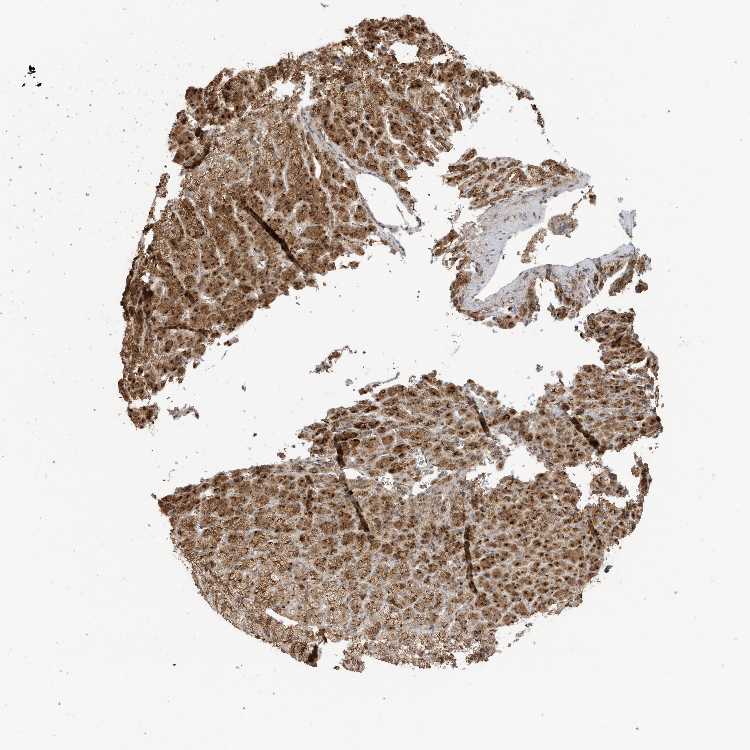

ADRENAL GLAND - Antibody stainingi

Antibody staining in the annotated cell types in the current human tissue is reported as not detected, low, medium, or high, based on conventional immunohistochemistry profiling in selected tissues. This score is based on the combination of the staining intensity and fraction of stained cells.

Each image is clickable and will lead to virtual microscopy that enables deeper exploration of all samples and also displays staining intensity scores, fraction scores and subcellular localization as well as patient and tissue information for each sample.

Antibody CAB037240

Glandular cells High